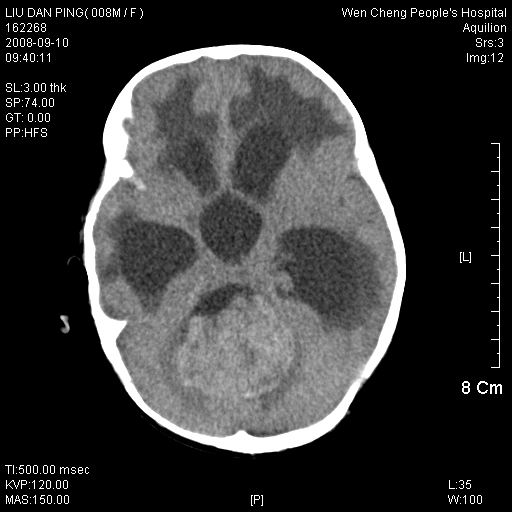

以下是引用深泽交通医院在2008-9-10 15:08:00的发言:[br]髓母瘤并脑积水

以下是引用卜一在2008-9-10 16:21:00的发言:[br]髓母细胞瘤伴梗阻性脑积水!支持![br]髓母细胞瘤特点:—般直径大于3.5cm,位于后颅凹中线之小脑蚓部。累及上蚓部的肿瘤延伸到小脑幕切迹之上,ct平扫肿瘤多呈均匀一致的高或等密度病灶,增强检查呈均匀一致的强化。病灶中有小坏死时,平扫亦可呈不均匀之混杂密度,注药后有增强。[br]

以下是引用yuhongjun在2008-9-10 16:57:00的发言:[br]髓母细胞瘤伴梗阻性脑积水.

以下是引用zjzjr在2008-9-10 15:09:00的发言:[br]髓母细胞瘤伴梗阻性脑积水.